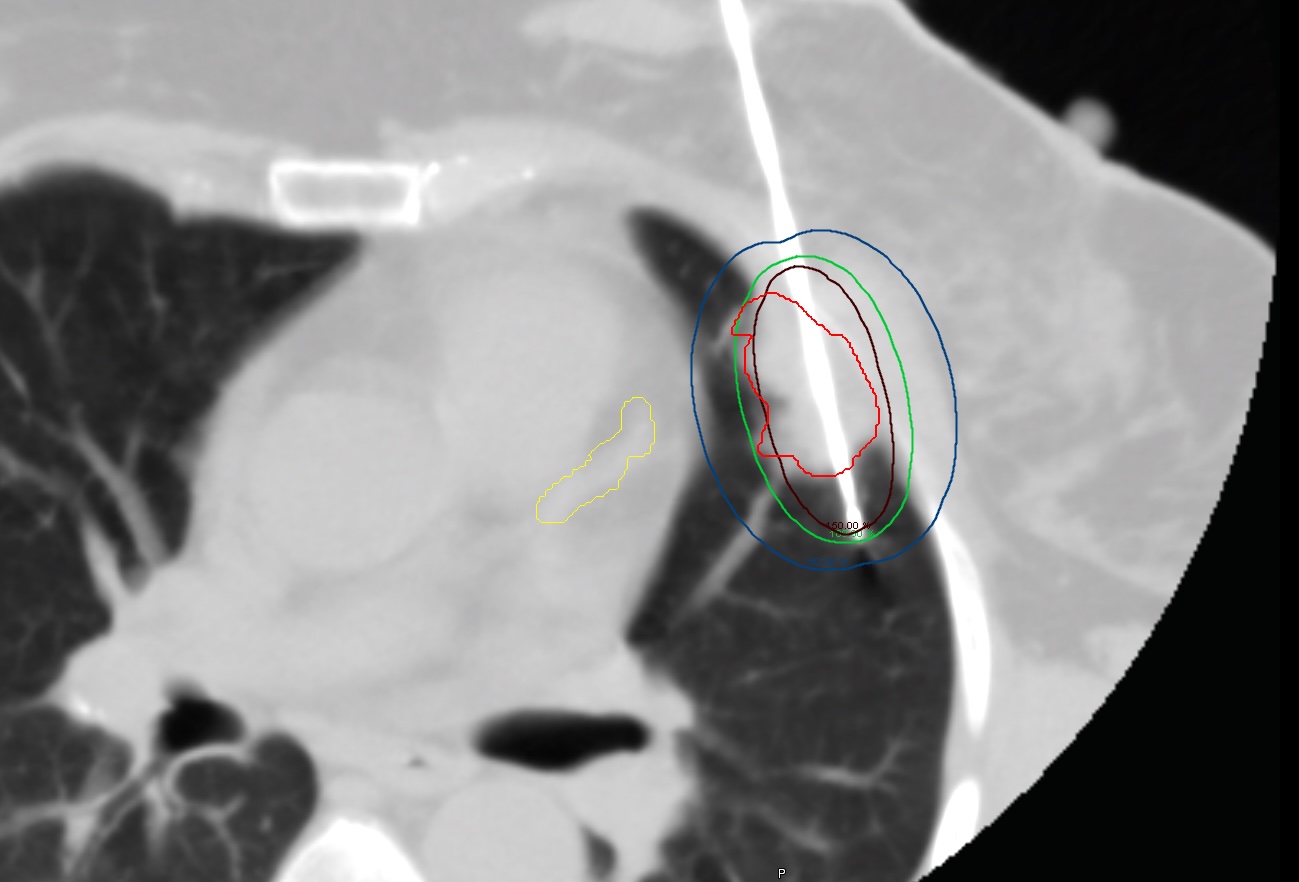

Advanced Liver and Lung Brachytherapy Treatment Setup

Lungs / Liver Cancer Brachytherapy

We provide cutting-edge brachytherapy for both primary and metastatic lung and liver cancers. Our advanced techniques ensure precise radiation delivery, improving treatment outcomes while reducing side effects for patients in Nepal. Learn More